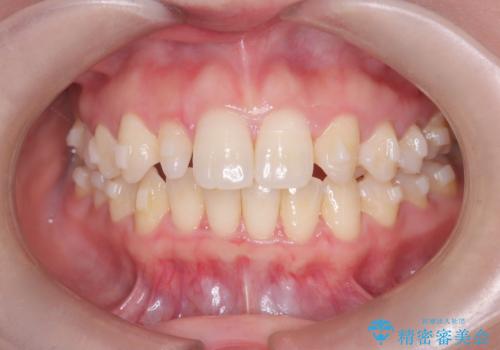

- 歯のデコボコと右上2番の歯の形が気になることを主訴に来院された患者様です。

軽度の叢生(凸凹)であったため、インビザラインのライトパッケージを用いて歯並びを改善しました。その後、右上2番はオールセラミッククラウンにより形態を回復し、審美性を向上させました。